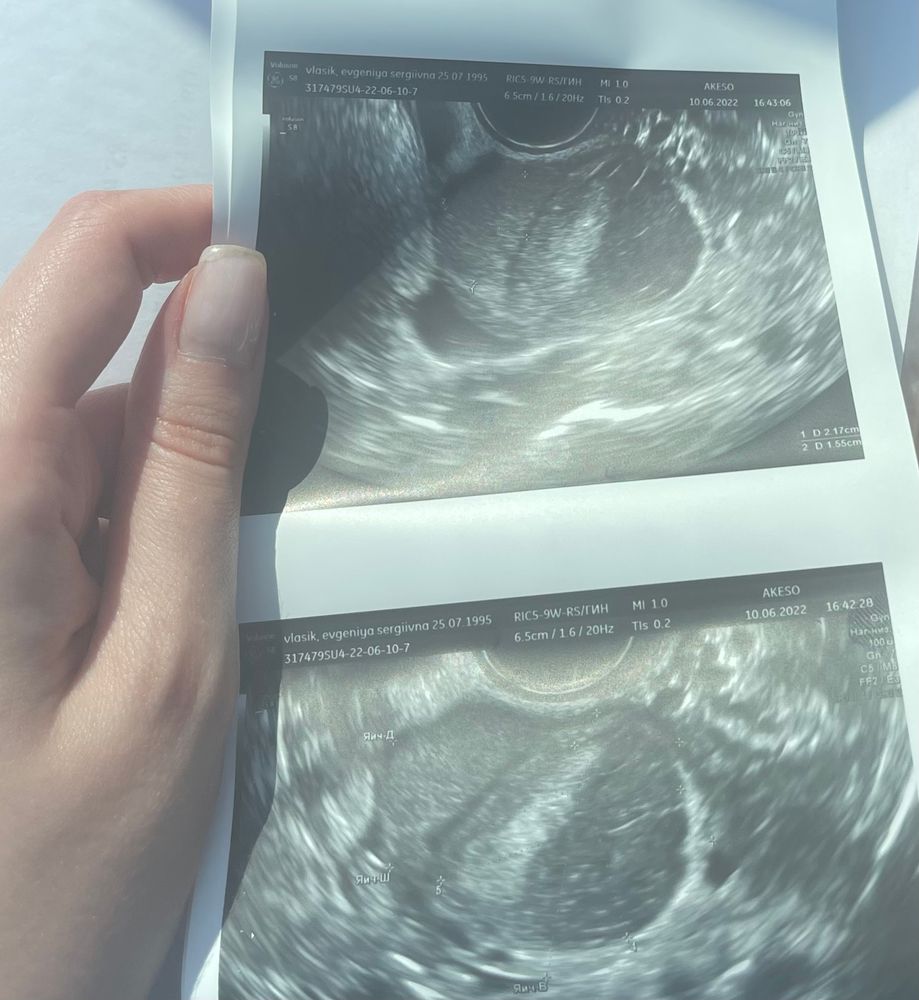

Впервые с декабря попала на узи.ДО декабря : эндометриома в ПЯ ~2,5см. СЕЙЧАС : +1 эндометриома в ЛЯ ~3.5см.

Итого , двусторонний эндометриоз 😕